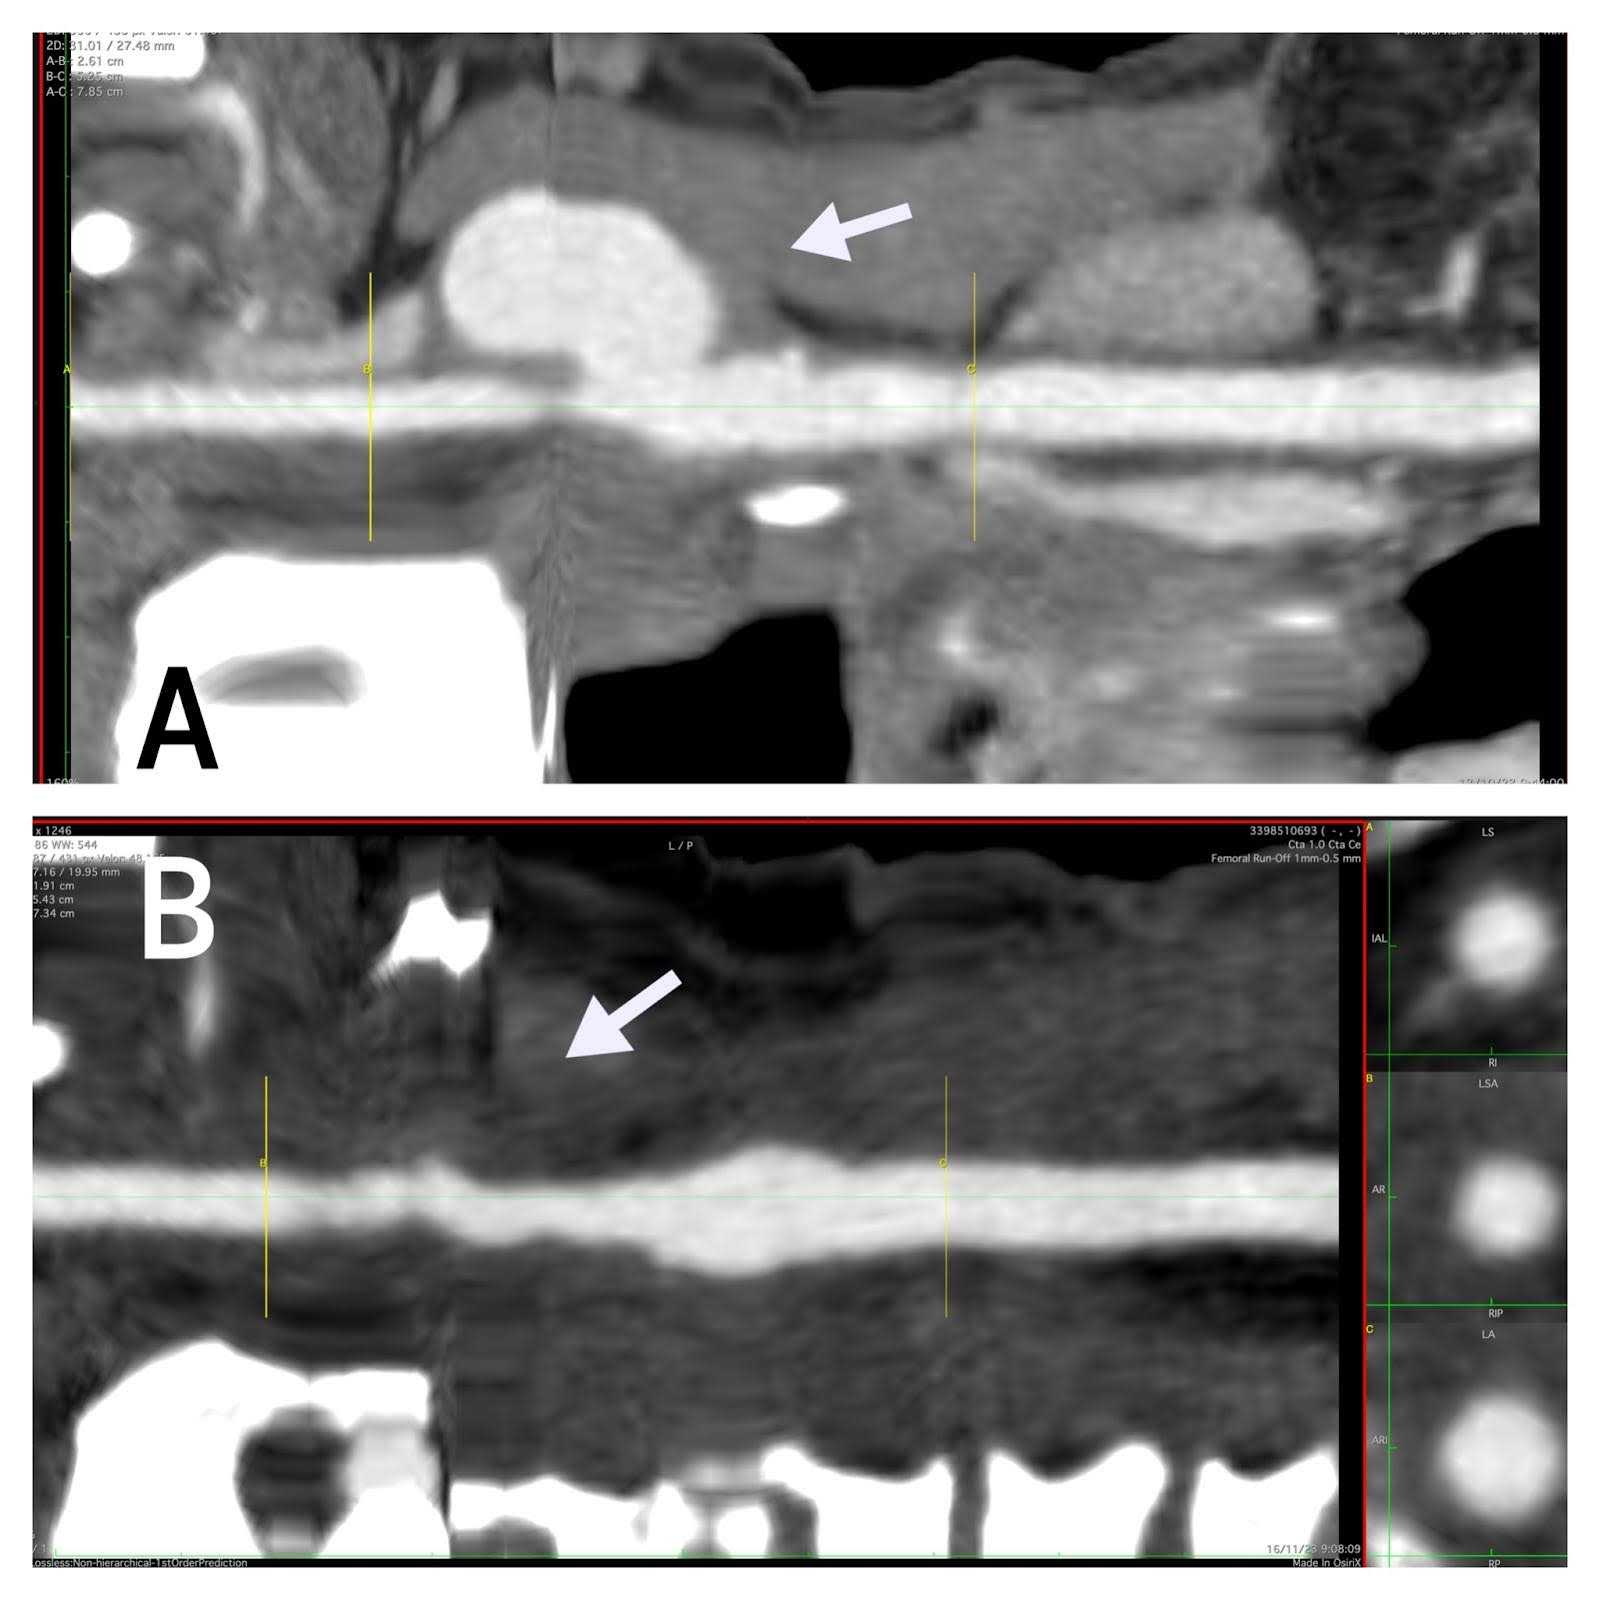

And it shows comparative reconstruction images (Figures 4 and 4) from common carotid artery to internal carotid artery before and after the intervention.

Figure 4. Comparative reconstruction before and after the intervention. (A) 3D comparative (arrow) reconstruction images from common carotid artery to internal carotid artery before surgery. (B) After the intervention.

Figure 5. Centerline Comparative. (A) Centerline comparative (arrow) reconstruction images from common carotid artery to internal carotid artery before surgery. (B) After the intervention.